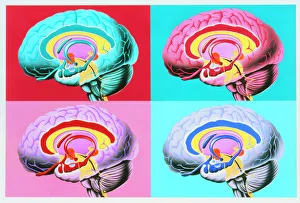

The central nervous system, the intricate network that governs our every thought and movement, is a marvel of complexity. From the delicate cerebellum tissue to the detailed light micrograph capturing its essence, we are reminded of its importance in maintaining balance and coordination. Anatomy comes alive as we explore the human brain from an inferior view. The intricacy of brain fibers is revealed through DTI MRI scans like C017/7099 and C017/7035, showcasing their vital role in transmitting information throughout this extraordinary organ. Artistic renderings bring us closer to understanding the medulla oblongata's significance within the brain. Its portrayal in various artworks allows us to appreciate how it controls essential functions such as breathing and heart rate. As we delve deeper into studying the central nervous system, models of the human brain provide invaluable insights into its structure and organization. Lateral views reveal countless regions responsible for cognition, emotion regulation, sensory perception, and motor control. Microscope slides offer glimpses into nerve cells' intricate architecture—a testament to their ability to transmit electrical signals at lightning speed. Meanwhile, glial stem cell cultures captured under a light microscope remind us of their crucial role in supporting neuronal function. Finally, artistic representations unveil the limbic system's enigmatic nature—an interconnected web responsible for emotions and memory formation. These captivating artworks allow us to visualize this complex network within our brains. Exploring these hints provides a glimpse into the awe-inspiring world of our central nervous system—the very foundation upon which our thoughts, actions, memories reside—reminding us just how remarkable our brains truly are.